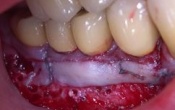

Double greffe gingivale libre sur les 2 canines mandibulaires en vue d'un traitement orthodontique

13/11/2009 | Commentaires (

7

)